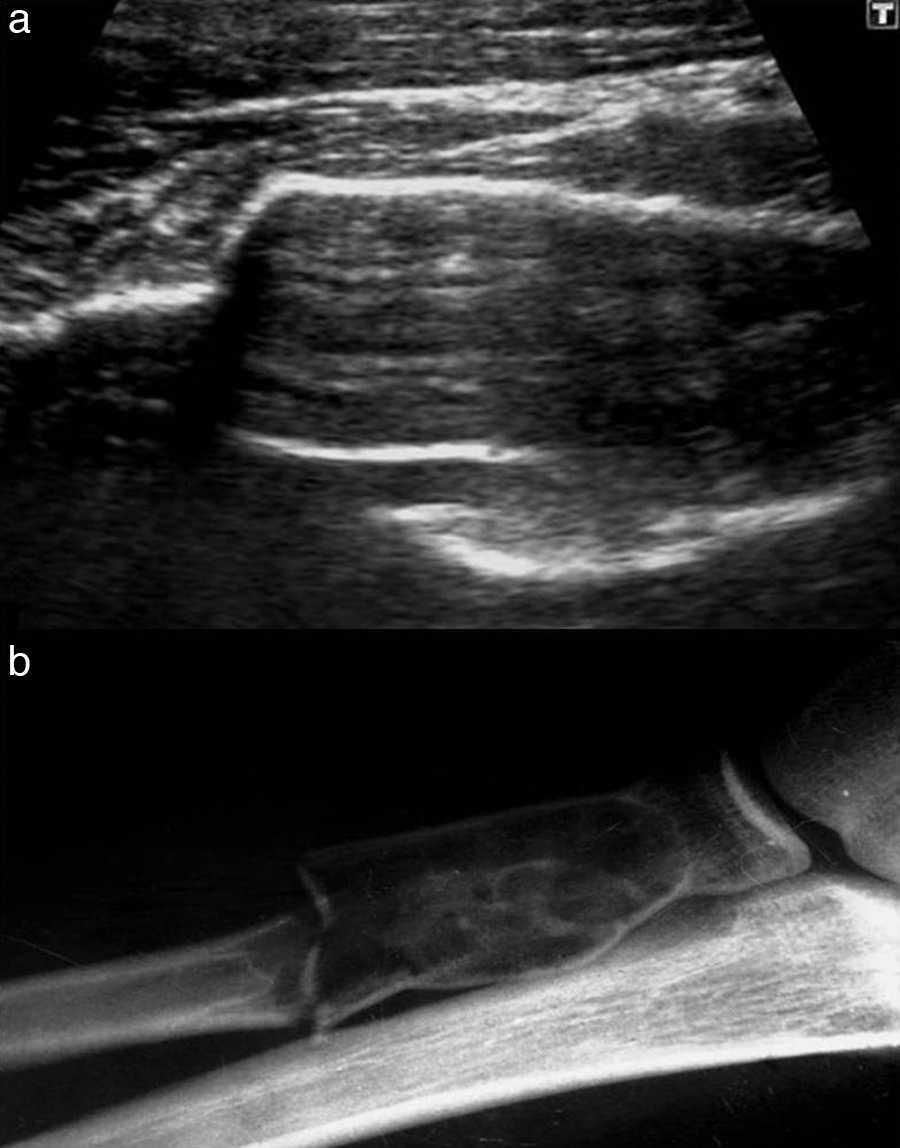

WebEcografía de Partes Blandas. El Tejido Celular Subcutáneo, en adelante TCS, es una de las estructuras que han aparecido en todas las imágenes de la Eco. WebResumen: La ecografía es una excelente herramienta para el diagnóstico de los tumores de partes blandas. Es con frecuencia la primera modalidad de imagen. WebLesiones que comprometen músculos, ligamentos, tendones, bolsas serosas, fascias y/o cartílagos. Generalmente se asocian a algún evento traumático. Se caracteriza por. WebRevisión del tema. Las masas y tumoraciones de partes blandas del tronco y extremidades representan un motivo de consulta frecuente en nuestro medio, pudiendonos encontrar. Web- lesión previa y recuperación deficiente La ecografía se está consolidando como la prueba de elección en los casos de las rupturas musculares y especialmente del control. WebLa ecografía es un estudio de partes blandas, en el cual se utiliza un equipo especializado que posee un transductor. Ese cabezal a su vez se encarga de.